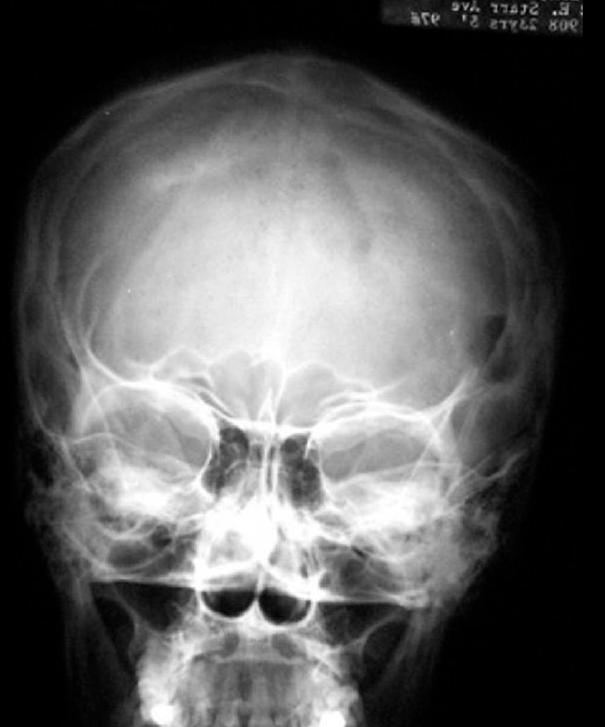

Рисунок 3. Эозинофильная гранулема костей черепа (рентгенограмма)

https://radiopaedia.org/cases/eosinophilic-granuloma-1